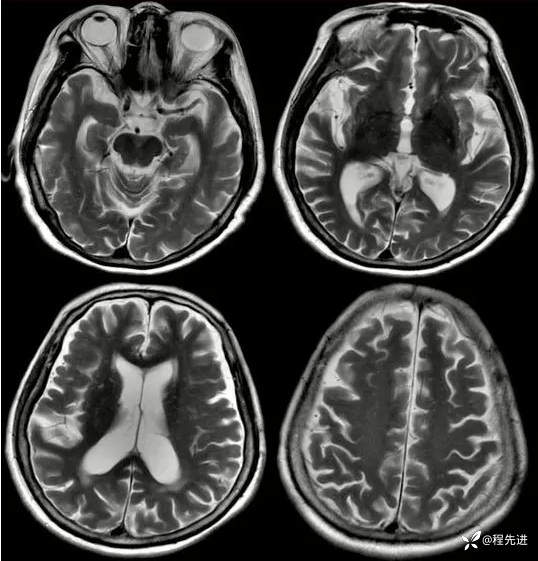

T2: